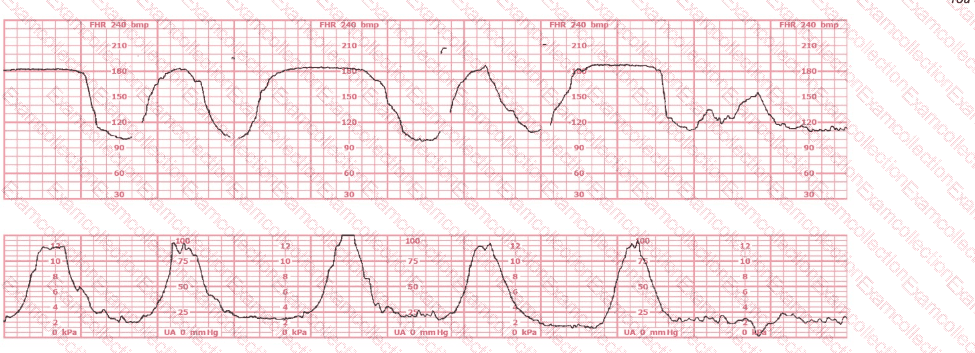

This fetal heart rate pattern is classified as Category III based on: